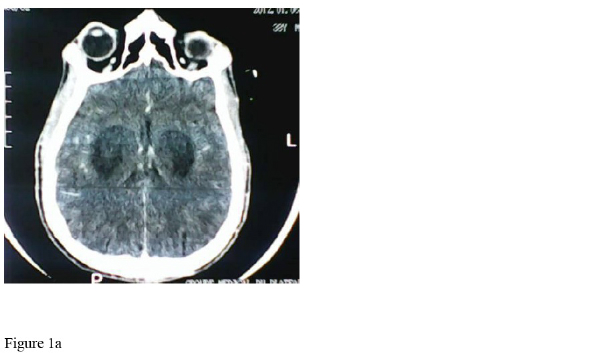

La Tomodensitométrie (TDM) cérébrale sans injection de produit contraste, met en évidence : deshypodensités bilatérales compatible avec une nécrose putaminale associées à de discrètes plages hypodenses frontalesbilatérales.

Hypodensités bilatérales putaminales (flèchespleines : 1a) associées à de discrètes plages hypodenses frontales bilatérales (flèches pointillées : 1b).

La tomodensitométrie (TDM) cérébrale a été demandée chez notre patient dans le cadre des désordres neurologiques prédominants et persistants (coma, agitations, cécité ...). Cette TDM a révélé : des hypodensités bilatérales compatibles avec une nécrose putaminale associée à de discrètes plages hypodenses frontales bilatérales, très caractéristiques d’une intoxication au méthanol.

Les lésions en neuroimagerie en rapport avec l’intoxication au méthanol ont été abondamment décrites et documentées [8]. Ces lésions sont les conséquences de l’agressivité du formate, métabolite du méthanol vis-à-vis du tissu nerveux. L’acide formique inhiberait le cytochrome oxydase de la chaîne respiratoire mitochondriale, induisant alors des lésions cytotoxiques d’origine hypoxique. Celles-ci prédomineraient au niveau de certaines régions vulnérables du cerveau : il s’agit des noyaux gris centraux, des voies optiques et certaines régions périphériques, sous corticales de la substance blanche. Leur répartition bilatérale, voire symétrique est fortement évocatrice [13,14].

S.Taheri et al [15] ont publié en 2010, une étude de cohorte ayant enrôlé 42 patients consécutifs victimes d’une intoxication aiguë au méthanol. Cette étude avait pour but de déterminer les anomalies retrouvées dans un tel contexte à la TDM cérébrale sans injection de produit de contraste et d’en évaluer leur signification pronostique. 28 (66,6%) patients présentaient des anomalies à la TDM cérébrale, pour un total de 55 anomalies TDM retrouvées. Chez 27 de ces patients, soit 96,4%, l’atteinte nécrotique putaminale bilatérale sous forme de lésions hypodenses à la TDM cérébrale était la forme la plus commune des manifestations. L’incidence des lésions hémorragiques était de 16,4%, un peu plus que les 13,5% dans la littérature. Le caractère hémorragique des lésions semble assombrir le pronostic.

L’atteinte nécrotique bilatérale du noyau lenticulaire plus ou moins associée à des atteintes nécrotiques de la substance blanche, surtout dans les couches périphériques sous corticales, sont la principale marque caractéristique en neuroimagérie de l’intoxication au méthanol. Ces atteintes peuvent toucher aussi le cervelet, l’hypothalamus. L’imagerie par résonance magnétique (IRM) apporte des constatations superposables à celles du TDM, s’agissant de la nature et de la localisation des lésions mais offre un avantage sur la TDM quant à la taille et la précocité de la mise en évidence des lésions [16,17]. Pour beaucoup d’auteurs, la TDM cérébrale peut apparaître normal à la phase précoce de l’intoxication, bien souvent un délai d’au moins 24 heures après la prise du méthanol parait nécessaire pour voir apparaître des lésions à la TDM cérébrale. Dans notre cas, la TDM cérébrale sans injection de produit de contraste a été réalisée au 6ème jour après la prise du toxique. Les lésions apparaissent très nettement caractéristiques. La signification pronostique de ces lésions – hors mis les lésions hémorragiques- est difficile à prédire. Même si elles signent une atteinte sévère, elles ne prédéterminent pas forcément une issue fatale ou défavorable. En effet dans la série de Taheri et al [15], 22 patients ayant eu des lésions à la TDM cérébrale ont pu recouvrer un état jugé satisfaisant et quitter l’hôpital. De même, Patankar et al [18], en 1999, dans une série de 4 intoxications au méthanol, signalaient 3 patients qui présentaient des anomalies caractéristiques à la TDM cérébrale, intéressant surtout les noyaux lenticulaires. Parmi eux, un décès est survenu, les deux autres ont recouvré un état de santé jugé satisfaisant et sans séquelle. Si l’atteinte bilatérale, voire symétrique des noyaux gris de la base du cerveau sont très caractéristiques de l’intoxication au méthanol, certaines affections métaboliques, toxiques ou dégénératives sont susceptibles de laisser des empreintes semblables au niveau des noyaux gris du cerveau [19]et il convient de ne pas les ignorer dans un contexte où l’imagerie prend une place centrale dans la démarche diagnostique : c’est le cas dans les intoxications au monoxyde de carbone, dans la maladie de Wilson, ou dans le maladie de Leigh.